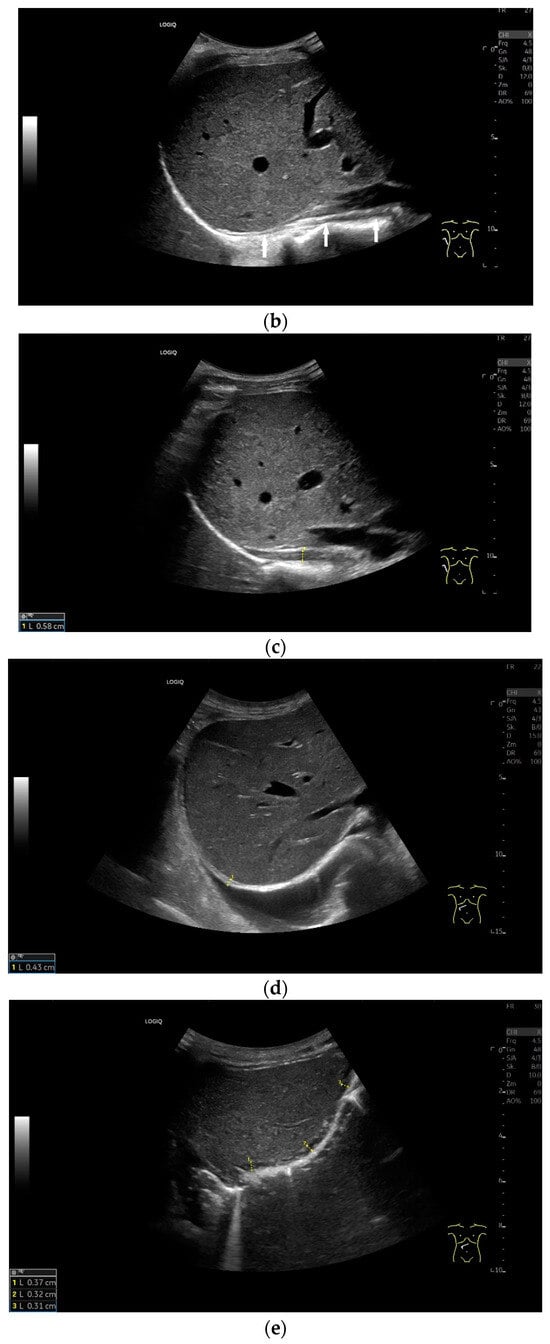

Lateral transducer position in the zone of apposition: The transducer is positioned longitudinally and laterally in the area of the mid-axillary line or slightly ventral to it between the anterior and mid-axillary lines, approximately in the 8th or 10th intercostal space. The diaphragmatic reflex is located on the inner side of the ribs below the pulmonary glide with pulmonary reverberations. This localization of origin of the diaphragm from the inner side of the rib cartilage is referred to as the zone of apposition (Figure 3). As this localization is only a few centimeters below the skin surface, high-resolution linear transducer use is highly recommended. In this position, the diameter of the diaphragm is measured during inspiration and expiration [2,3,4,5] (Figure 4). The thickness of the diaphragm varies, with caudal parts being thicker than cranial parts. The measurement of diaphragm thickness is highly variable depending on the intercostal space chosen, with thickness varying by up to 6 mm between the intercostal spaces [6]. It is therefore important to select the same position for comparable measurements and, if necessary, to mark the location for the transducer position [7]. Obesity limits assessment of the diaphragm [2].

To assess the diaphragm and its function, the diaphragm’s thickness, contraction and excursion are determined. Diaphragm thickness is mainly measured in the zone of apposition and excursion in the subcostal position. The diaphragm thickness is measured at end-expiratory (Tendexpir) and end-inspiratory (Tendinspir) points. Expiratory and inspiratory measurements should be taken with exactly the same transducer position. The measurement is taken at the outer edges of the hypoechoic muscle and at an angle of 90° to the diaphragm’s surface (Figure 4).